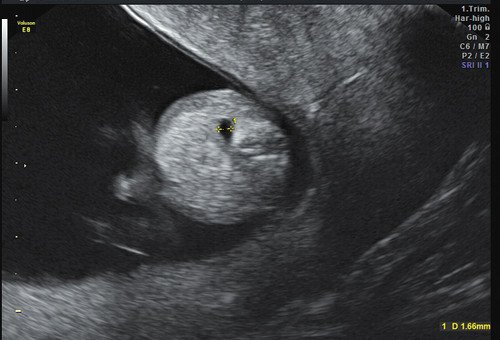

Пациентка Д. 34 лет. Беременность третья, в анамнезе 2 неразвивающиеся беременности на ранних сроках гестации. Муж соматически здоров, брак неродственный. У женщины прооперированные в детстве врожденные пороки развития лица и конечностей: расщелина верхней губы и неба, коррекция синдактилии-эктродактилии кистей и стоп (рис. 4). Беременная обратилась в медико-генетическое отделение МОНИИАГ для проведения скринингового осмотра в первом триместре беременности. При ультразвуковом исследовании выявлено: беременность 13 недель; латеральная расщелина верхней губы (рис. 5), эктродактилия стоп (рис. 6). Проведено медико-генетическое консультирование по предварительному пренатальному диагнозу "синдром ЕЕС". Семья приняла решение пролонгировать беременность. Родился доношенный мальчик весом 2900 г, рост 49 см, оценка по шкале Апгар - 7/8 баллов. Все описанные пренатальные пороки развития подтверждены. Учитывая то, что в этом случае синдромом ЕЕС больна и сама женщина, это унаследованная форма синдрома ЕЕС.

Рис. 5. Латеральная расщелина лица у плода в 13 недель.

Рис. 6. Эктродактилия стопы у плода в 13 недель.